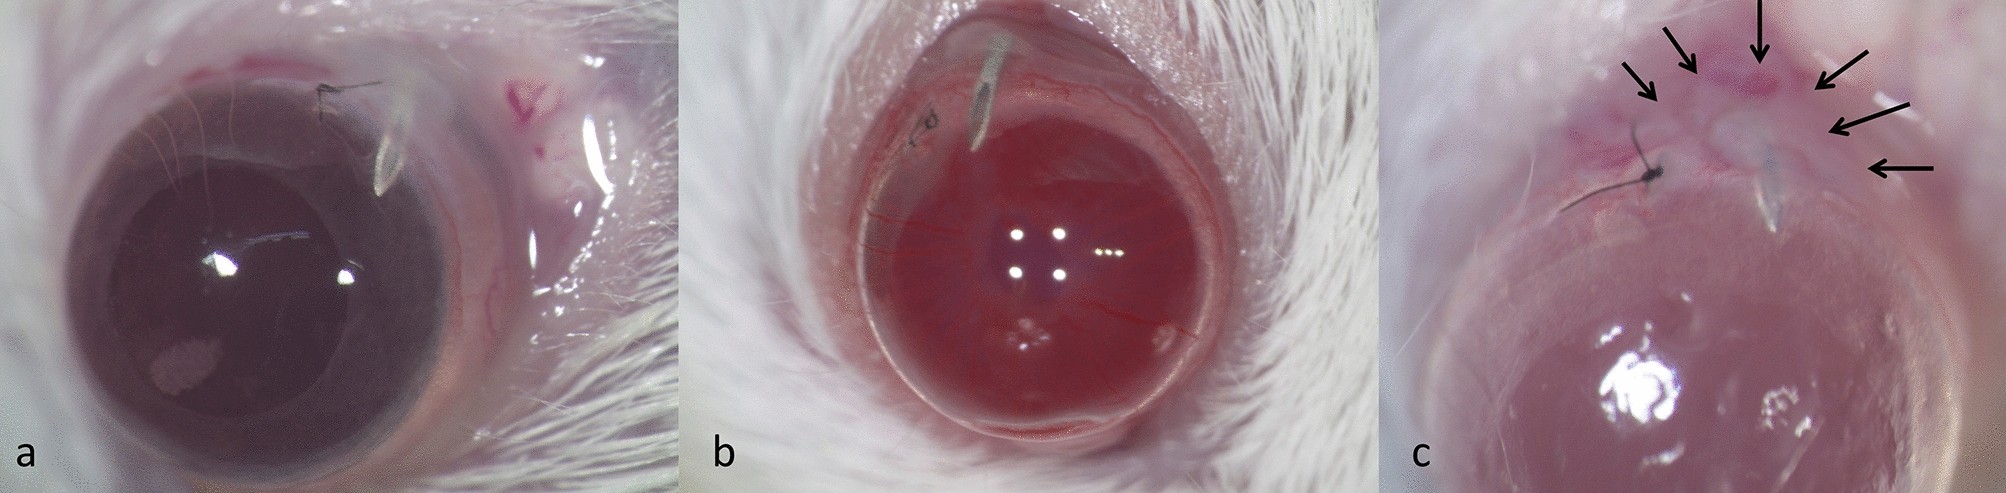

Photographs of mouse eyes after filtration surgery. Photograph of mouse eyes one day (a), three days (b) and seven days (c) after filtration surgery. At day 1 and day 3, the bleb was maintained, but at day 7 the bleb region was encapsulated (arrows).